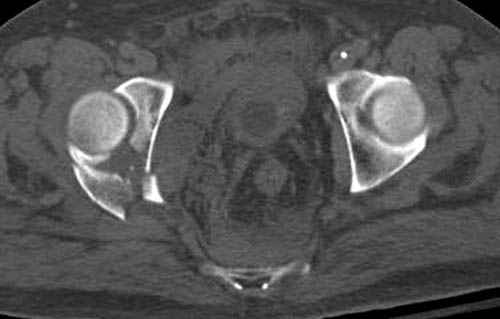

Прооперирован вчера на 13 день после поступления.

Больному 41 и из-за гемодинамической нестабильности в течение первых 7 дней был в реанимации под интубационной седацией.

Кроме перелома плеча у больного старый дистракционный перелом T12-L1 оперированный когда-то и кем-то, открытый перелом костей предплечья, который был прооперирован в ночь поступления, после I&D (хирургической обработки). Из-за разрыва селезенки при поступлении травма хирургами произведено удаление.

Дополнительно имеется перелом ацетабулума: задняя

колонна с полупоперечным переломом, и переломы костей лица.

На седьмой день зафиксирован перелом ацетабулума через задний доступ. Перед операцией для профилактики DVT, IVC фильтер, также получает Lovenox.

Извиняюсь за качества снимков, обычный больной в 300 фунтов, портативным ренген аппаратом не пробить.

Очень хорошаая работа, поздравляю! Хотелось бы увидеть снимок таза до операции. Каким образом и как долго предполагаете разгружать тазобедреннй сустав в дальнейшшем?

Отправитель: Evgueny Tchekashkine 30 Ноябрь 2007, 16:57

По возможности вышлите снимки, сканы таза до реконструкции, интраоперационные.

По снимку создается впечатление о высоком поперечном переломе, задней колонны, стенки; почему не пользовались *magic screw*?

По возможности вышлите снимки, сканы таза до

реконструкции, интраоперационные.

Там множество обычных 2.7 мм шурупов, потом идет фиксация основными пластинами.

Снимки здесь....